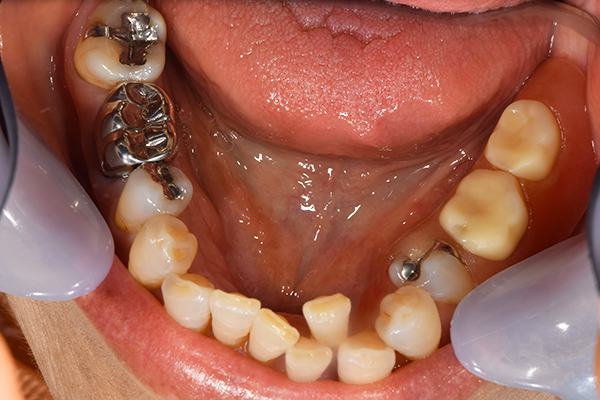

ケース4

(アタッチメントを用いた部分入れ歯)

右上のインプラント周囲炎で、その部分が痛いという患者様でした。 また奥歯で噛むことが難しかったため、前歯を使用することが多くなり、 前歯が前よりも前に出てきていることも気になっていらっしゃいました。

インプラント部以外にも歯周病が進行していましたので、歯周病の治療を行いました。 残念ながらインプラントと、1本の歯が残せなかったため抜歯を行いました。 その後、前歯の出っ張りを修正することと入れ歯の安定を図るため、残っている歯を全てかぶせ物にしていくことになりました。 写真中央は抜歯後に入れた治療用の入れ歯になります。 抜歯後歯ぐきが安定しましたら、入れ歯とかぶせ物の型取りを行いました。

噛み合わせチェックでしっかり奥歯で噛めるようにし、 歯を並べます。 その後、それに合わせて前歯を作っていきます。

最終的な入れ歯用の型取りをします。 シリコンで精密に型取りができました。

こちらが完成したかぶせ物と入れ歯です。かぶせ物にはアタッチメントをつけて金属のバネが見えない構造になっています。 入れ歯自体も金属を使用して、極力違和感がでないように、薄く作成しました。

お口の中に入れた状態です。 非常に見た目もよい出来となりました。 バネがみえないと見栄えが全然ちがいます。

年齢 70代・女性

主訴 奥歯のインプラントが痛い。

前歯がでてきた。

治療期間 6ヶ月

治療費 .メタルボンドクラウン7本:770,000円

.アタッチメント2個:220,000円

.義歯:550,000円

治療方針 ゆれてきたインプラントを抜去した後、歯周病の治療と、予後不良の歯を抜歯して、義歯を作成します。

抜歯後は治療用の入れ歯を作成し、ものが噛める様にします。

また前歯は、被せものをすることにしました。

治療内容 右上のボーンアンカードブリッジ(インプラントのブリッジ)部分がインプラント周囲炎になり、ぐらぐら揺れてきました。

そのため、インプラントを抜去した後、歯周病の治療と、予後不良の歯を抜歯して、義歯を作成していきました。

見た目が入れ歯とわからない様に針金のない、アタッチメントを使用した入れ歯を作成することにしました。

抜歯後は奥歯でものが噛める様に治療用の入れ歯を作成しました。

また前歯はフレアアウト(奥歯で噛めなくて前歯で噛む様になって、前歯が前に出てくる現象)していたため、患者さんの希望でかぶせ物をすることにしました。

特記事項 歯やインプラントを抜いた後は、2〜3ヶ月歯ぐきの回復を待ってから入れ歯を作るため、待機期間があります。その間、治療用の入れ歯を調整しながら使います。かぶせものをした後は歯がしみたり、場合によっては神経を抜く処置が必要になることもあります。